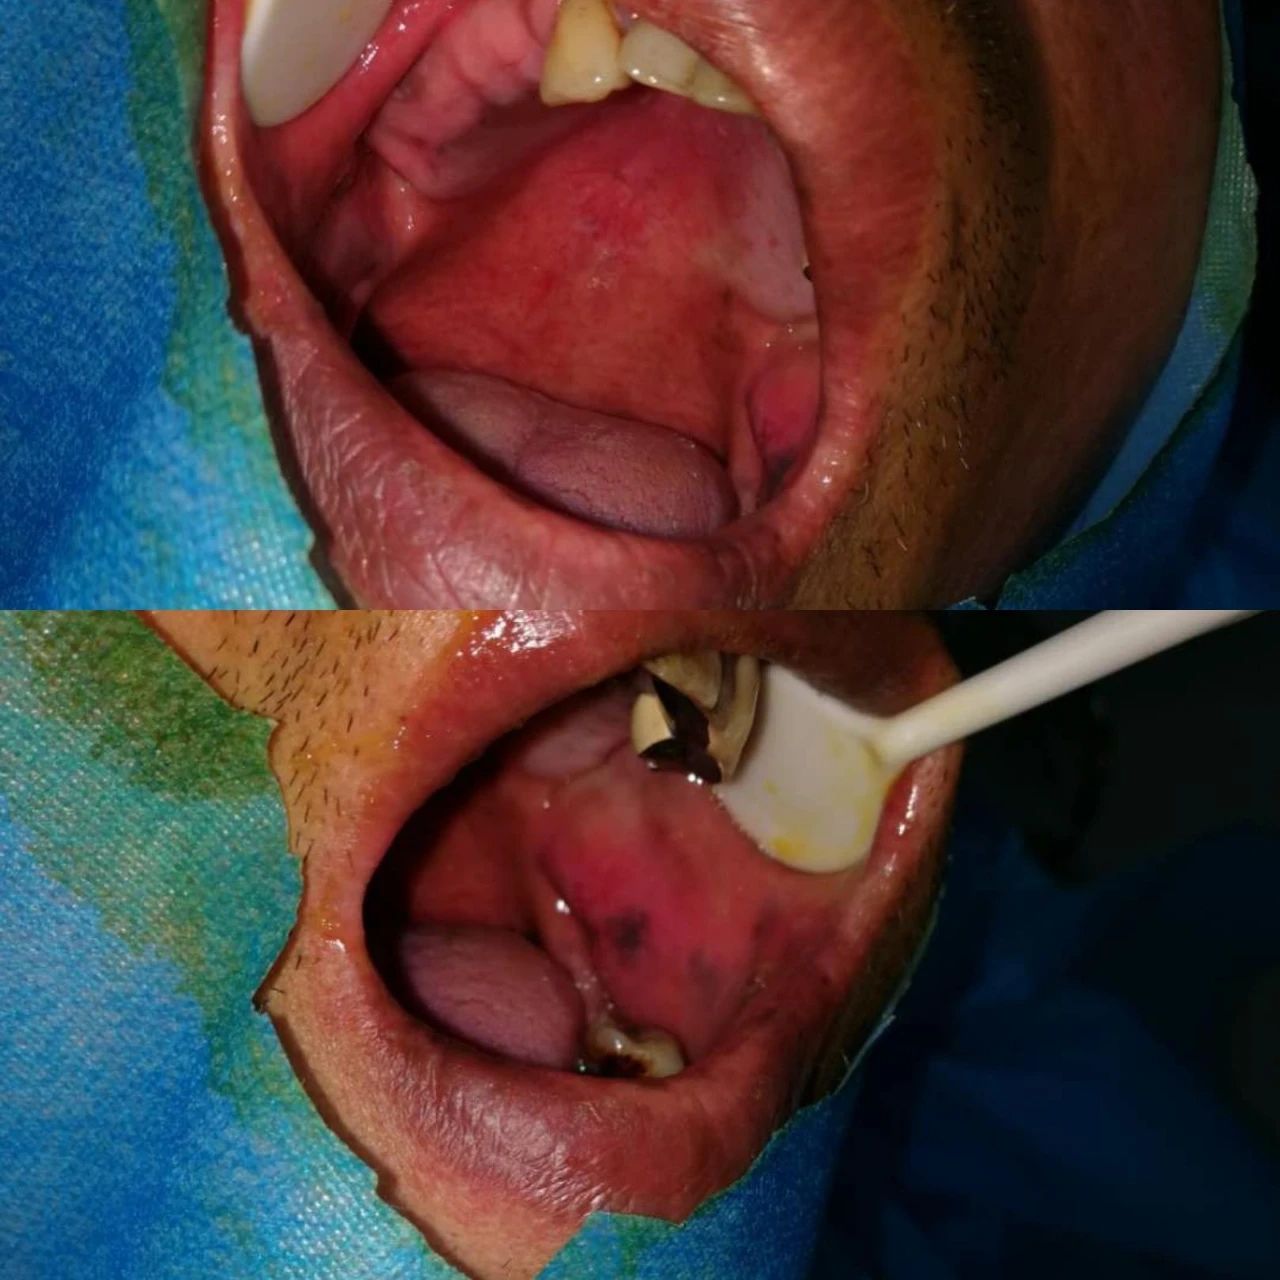

此次培訓(xùn)是由美國(guó)哈佛大學(xué)牙學(xué)院博士張杰發(fā)起,江陰金泰克生物技術(shù)有限公司舉辦的。張杰博士和山西省口腔醫(yī)學(xué)會(huì)副會(huì)長(zhǎng)鄭強(qiáng)教授、金泰克旗下門診醫(yī)師張乙云共同為學(xué)員們呈現(xiàn)了一場(chǎng)精彩的口腔學(xué)術(shù)盛宴。種植技術(shù)示范現(xiàn)場(chǎng),鄭強(qiáng)教授和張乙云醫(yī)師一小時(shí)內(nèi)為患者種植牙15顆,現(xiàn)場(chǎng)觀摩學(xué)員無(wú)不對(duì)金泰克種植體系統(tǒng)先進(jìn)的設(shè)計(jì)原理和簡(jiǎn)易的操作方法表示稱贊。

(學(xué)員現(xiàn)場(chǎng)觀摩鄭強(qiáng)教授手術(shù)示范,一小時(shí)內(nèi)完成15顆種植牙)

手術(shù)過(guò)程時(shí)間持續(xù)一個(gè)小時(shí),患者缺失的主要為后牙部分,情況復(fù)雜,難度較高,術(shù)后無(wú)不適狀況,面部無(wú)腫痛。